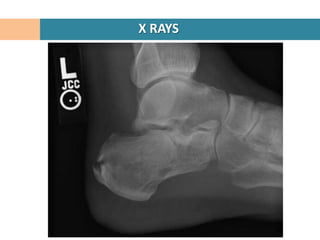

X RAYS

Lateral Hind foot

Confirms diagnosis of calcaneal #

Crucial angle of Gissane

Tuber angle of Boehler

Intraarticular #

Loss of ht of post facet

Reduced Boehler angle

Increased Gissane angle

Joint Depression vs Tongue type